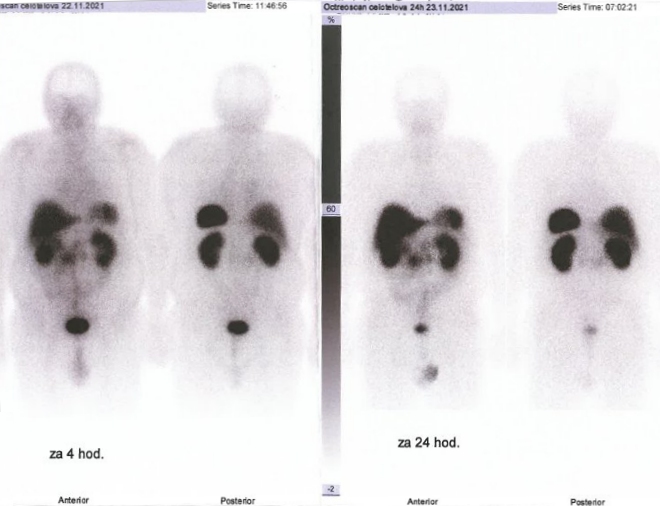

Scintigrafie Octreoscanem:

I. v. jsme aplikovali 190 MBq analogu somatostatinu značeného 111In

(přípravek OctreoScan firmy Curium Netherlands

B.V.) a provedli pomocí hybridní tomografické scintilační kamery Symbia T2 firmy Siemens opatřené kolimátory pro střední energie planární celotělovou scintigrafii a cílenou tomografickou scintigrafii (SPECT) břicha a pánve kombinovanou s CT za 4 a 24 hod.

(obr. 1-3).

/ Obr. č. 1: Celotělová scintigrafie 4 a 24 hod. po aplikaci OctreoScanu.

Popis: Prokazujeme dva okrsky patologicky zvýšené hustoty somatostatinových receptorů v paketu LU na mesenteriu vpravo ve výši L2 a v LU v retroperitoneu paraortálně vlevo ve stejné úrovni - svědčí nejspíše pro metastázy NET.